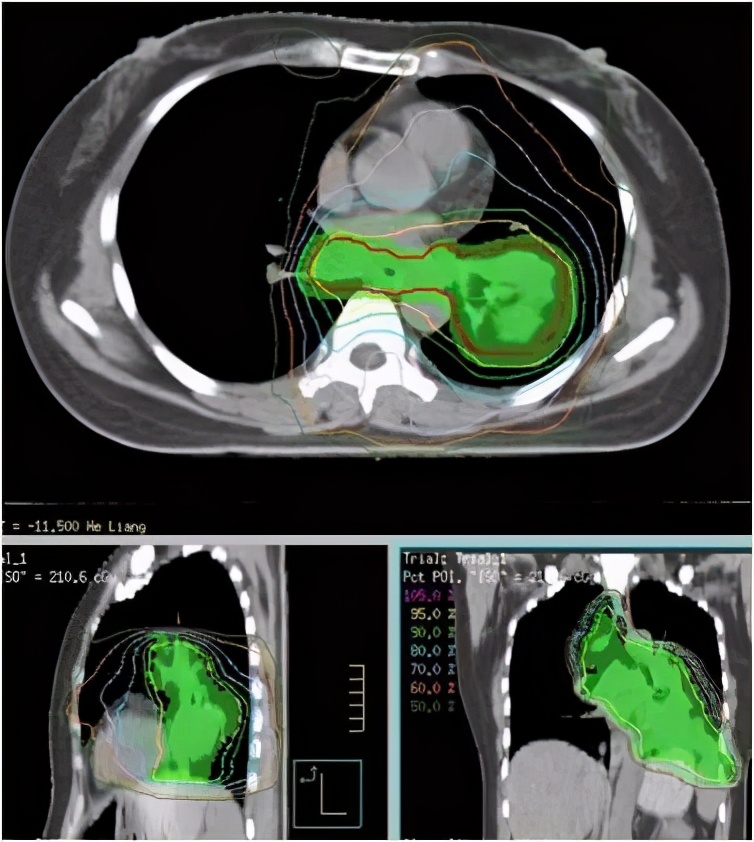

2020-09-04、2020-09-25给予肺部转移灶+纵膈淋巴结低剂量放疗联合白蛋白紫杉醇化疗及PD-1抗体免疫治疗两次,每次放疗处方剂量:2Gy/1fd1,白蛋白紫杉醇300mgd1,PD-1抗体240mgd2,每三周一次。

我们给患者设计的治疗方案特殊之处:该患者采用每周期仅2Gy低剂量放疗涵盖所有肺部及纵膈病灶,旨在招募化疗药物和免疫细胞到肿瘤病灶区域,联合纳米药物化疗药,促进肿瘤抗原释放,PD-1抗体促进免疫抗肿瘤效应,结果是成功缓解了难治性耐药肿瘤,并且未发现明显不良反应。患者治疗后咳嗽、胸闷症状明显缓解,显著改善了生活质量。